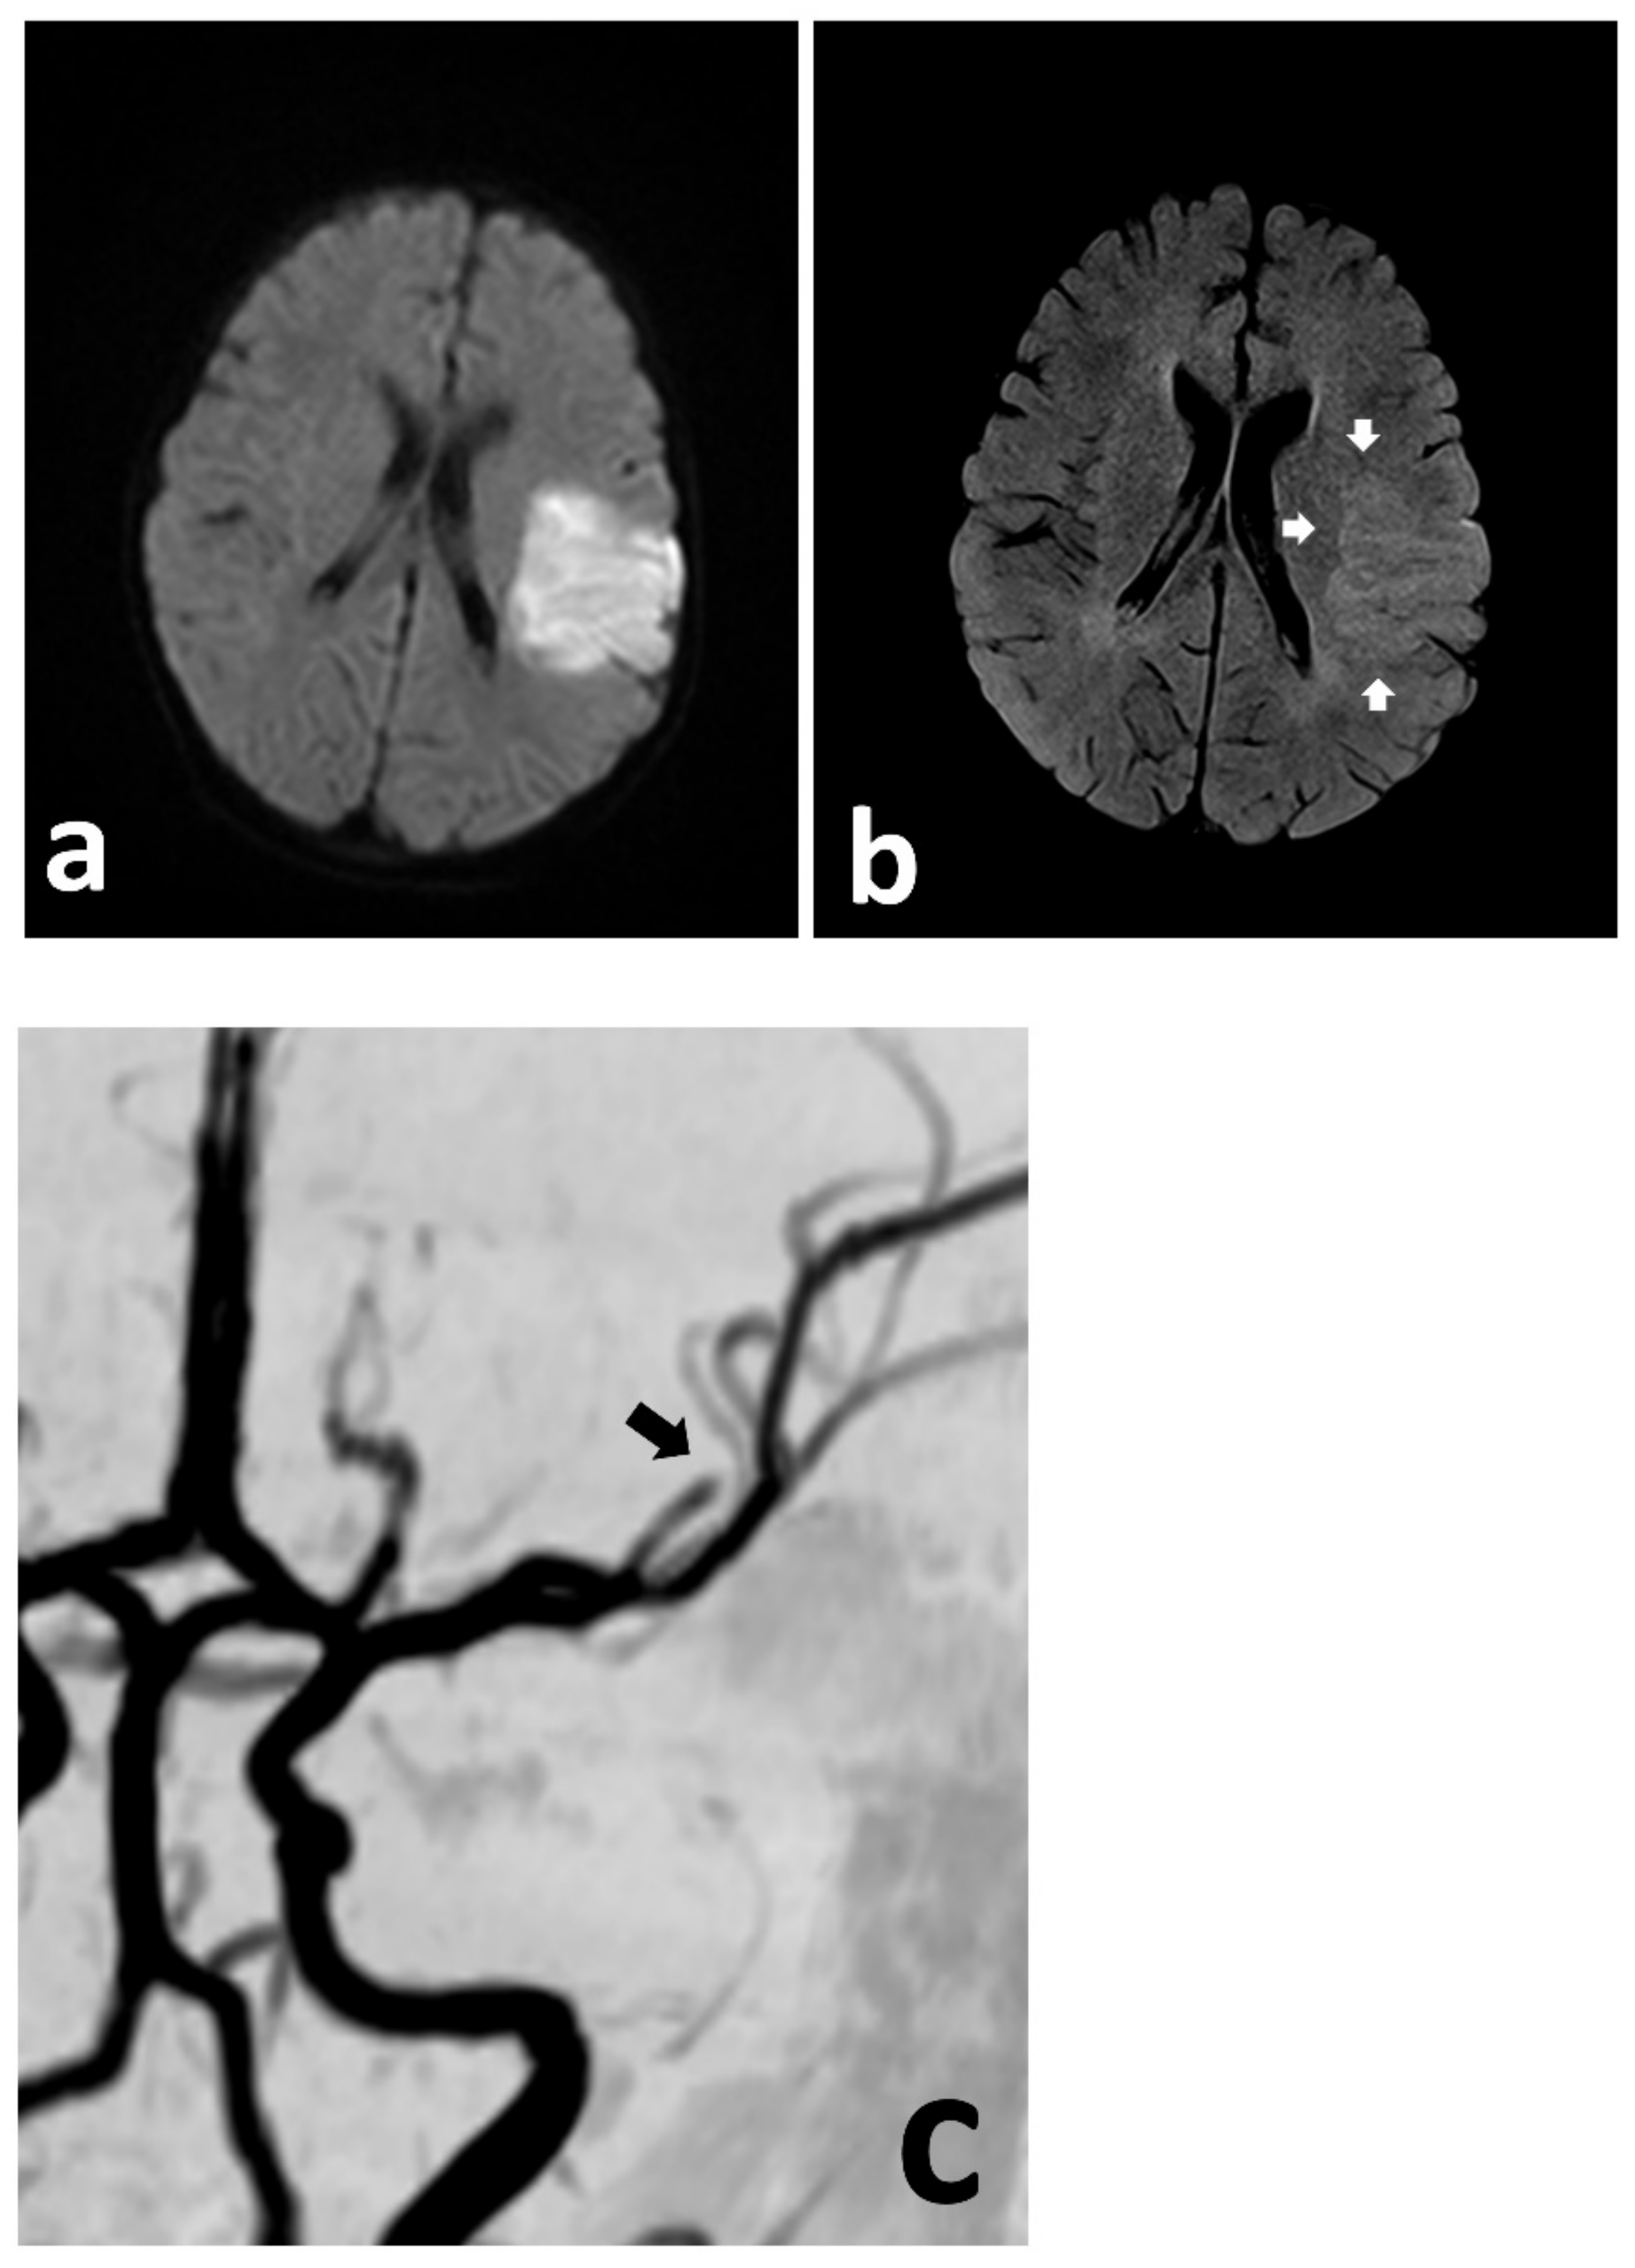

Figure 1.

Urgent MRI study demonstrating focally restricted diffusion in the MCA (md) territory (a), with only discrete hyperintensity in the FLAIR sequence (b) (white arrows), indicating at least a partial mismatch. The MRA demonstrates cut-off of the MCA (md) (c) (black arrow).